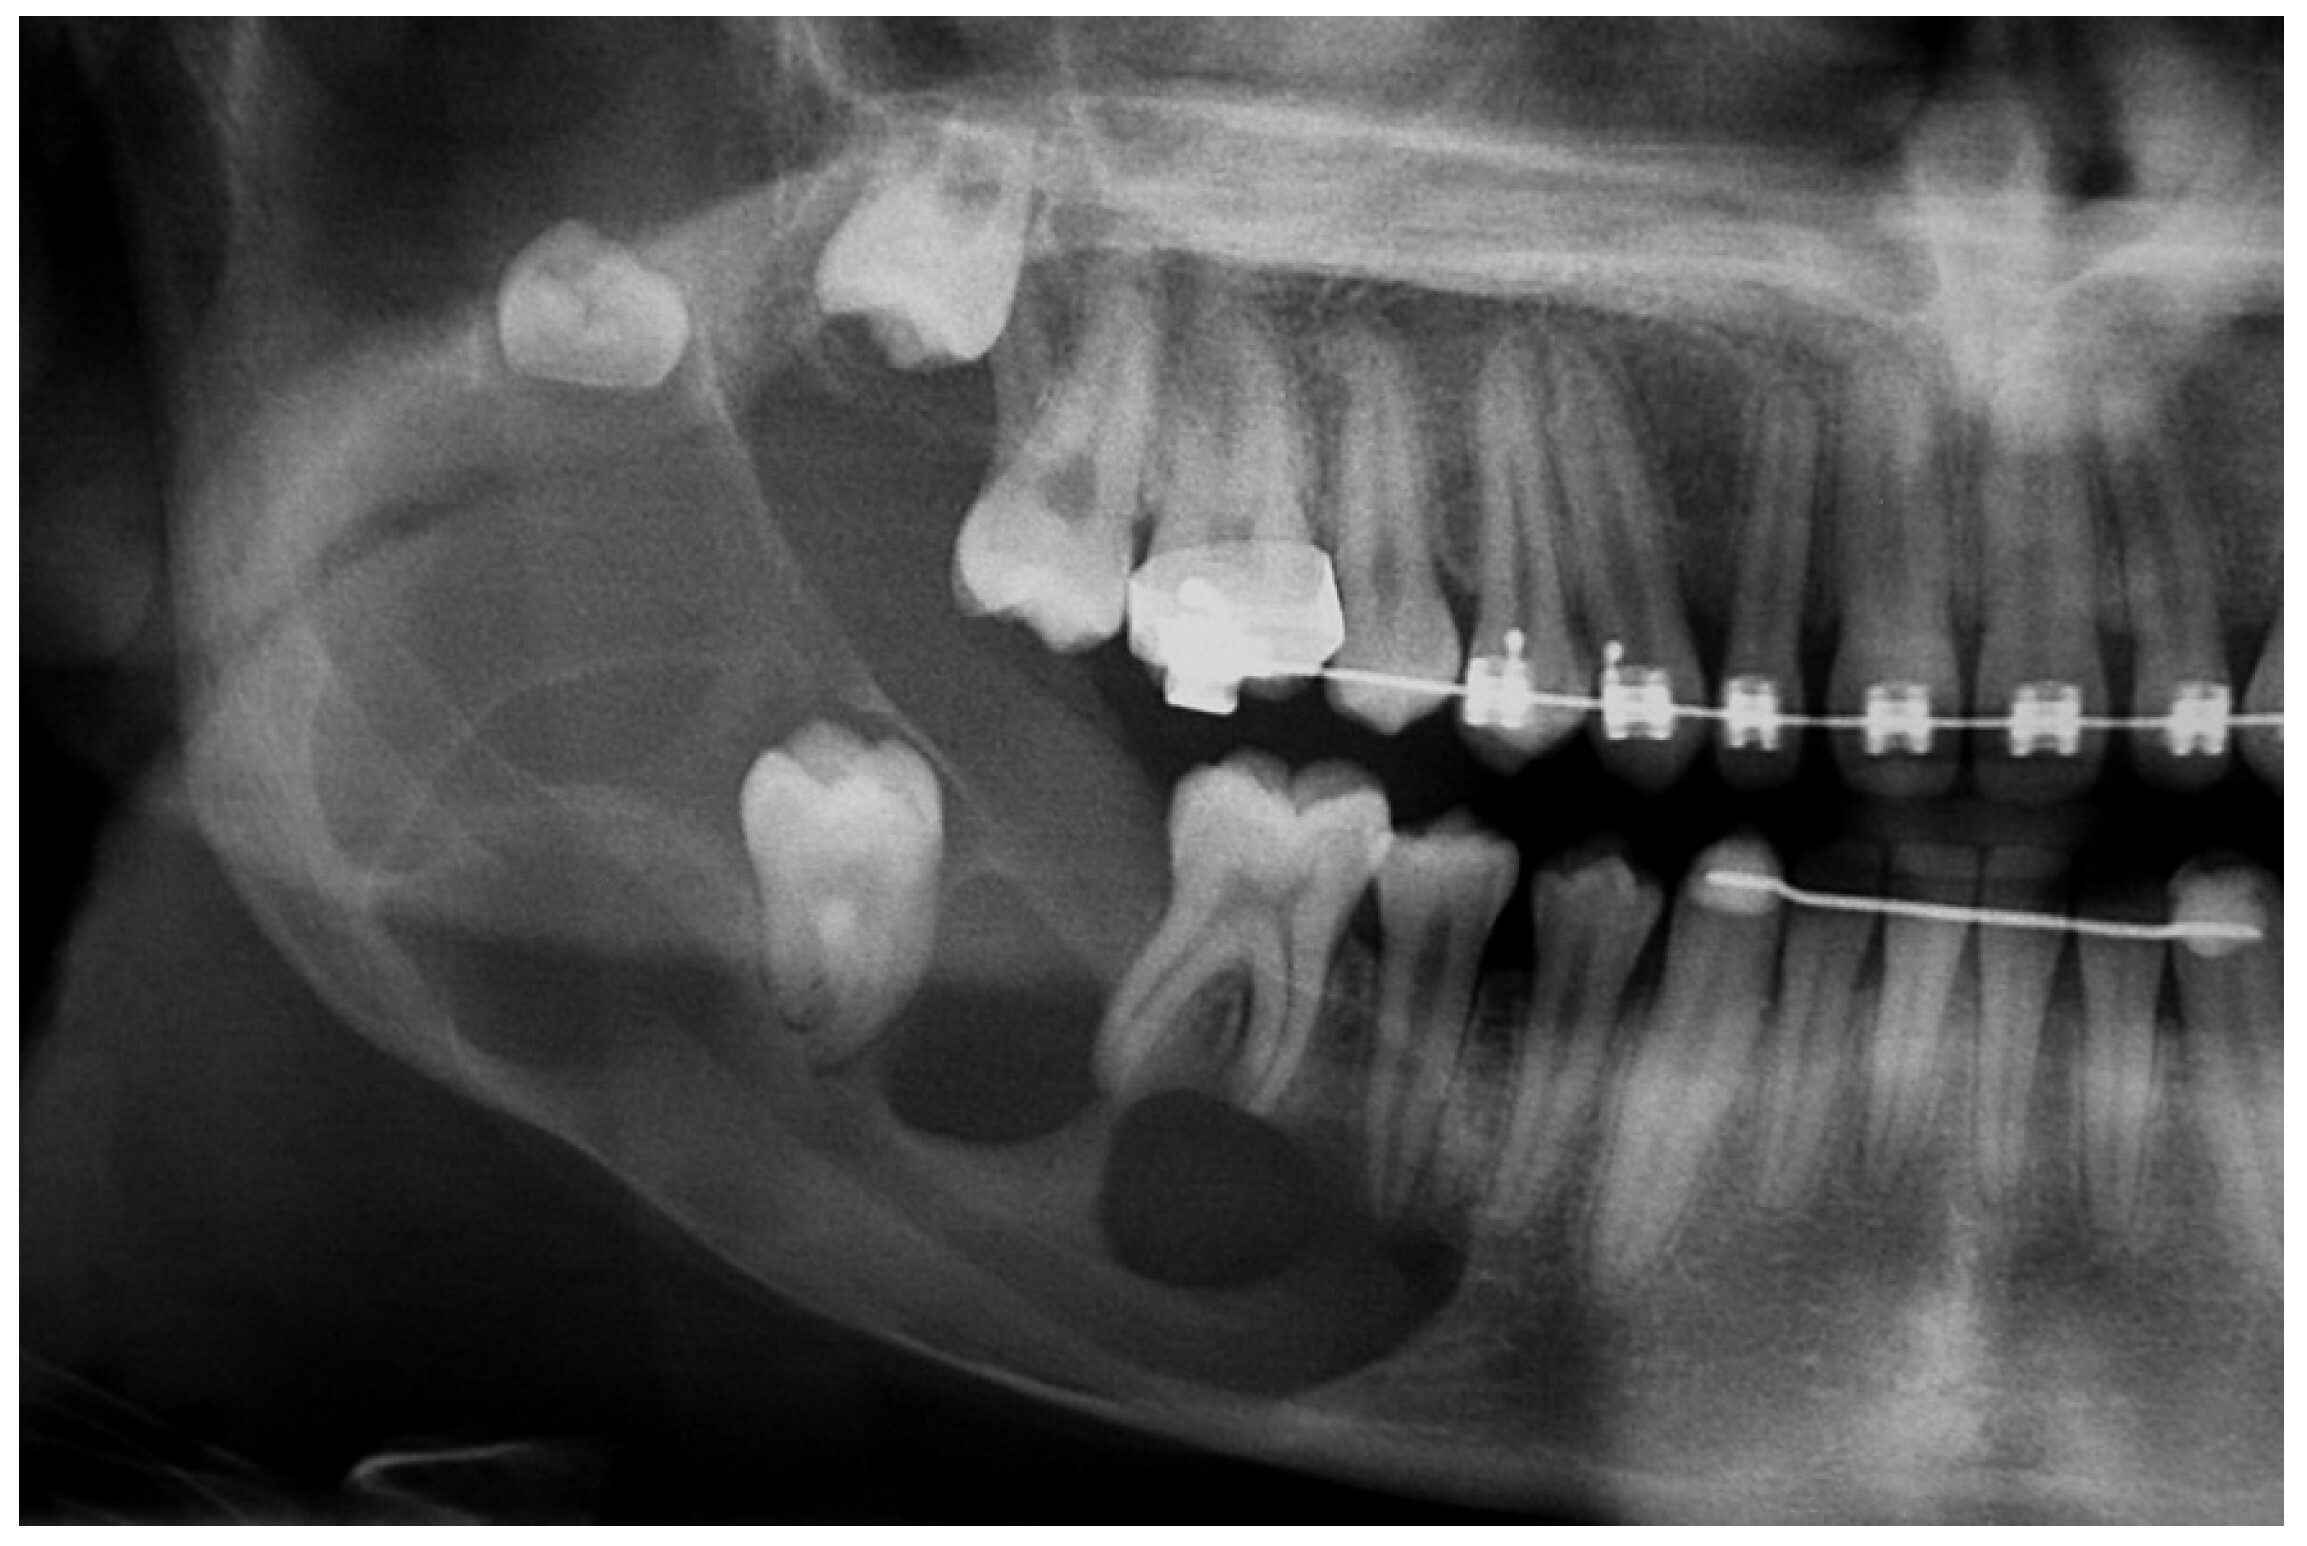

Because these cysts grow slowly and are often near the back of your mouth, you probably wouldn't even know one is there until your dentist tells you about it. They could see it in a routine examination. If your dental professional is checking on your wisdom teeth coming in, they may use a radiograph (x-ray) and discover it, or an orthodontist may notice a dentigerous cyst during a consultation for braces or clear aligners.

These growths can get big enough that you would feel it, but that is rare. If you have a larger cyst, it could impact the teeth on either side of the growth, adversely affecting the roots of those teeth and potentially even moving those teeth out of position.